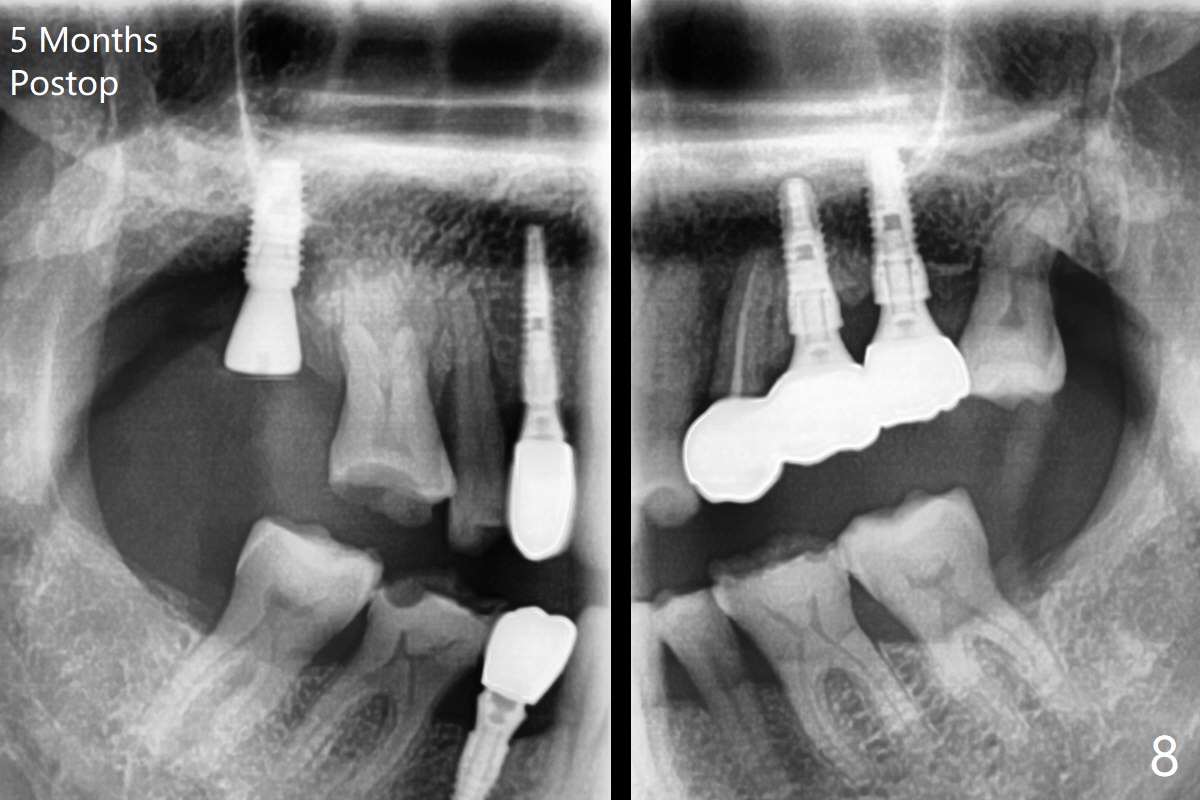

Two things happen immediately before this surgery. A SM implant is found to fail related to bruxism and poor oral hygiene, ~ 5 years in function; a UF implant will be used instead. DIO Sinus Approach Kit has not been autoclaved; therefore the free-hand one has to be used with caution. In fact the procedure goes on apparently smoothly in spite of the fact that the patient with medical knowledge is nervous about the risk of sinus lift. After 4.0x8.5 mm Neo Navi drill with 12 mm offset, the 3.6 mm sinus safety drill is used from 7 to 9 mm in length, followed by water balloon, PRF membranes (x2) and mixture of autogenous bone graft and allograft and 4.5x10 mm dummy implant (Fig.1). The definitive implant is placed with satisfactory stability (Fig.2), but a 6.5x7(4) mm healing abutment is close to the mesial crest (*). The former is reloaded following 6.0 mm Bone Profile Drill (Fig.3) and then is changed to a 6x6 mm IS one. The patient reports nasal hemorrhage immediately returning home, but there is no similar episode a few hours later. Re-analysis of preop (Fig.4) and immediate postop (Fig.5) CT shows that water balloon technique in fact swells the sinus membrane (M) instead elevating it. It is safe to place more bone graft (Fig.5 *). There is pain when the 6x6 mm healing abutment is being removed nearly 5 months postop (Fig.6.7). The patient complains of mild sinus discomfort, although panoramic X-ray does not show abnormality (Fig.8). He will return for recheck for implant stability (low bone density) before impression 2-4 months later.